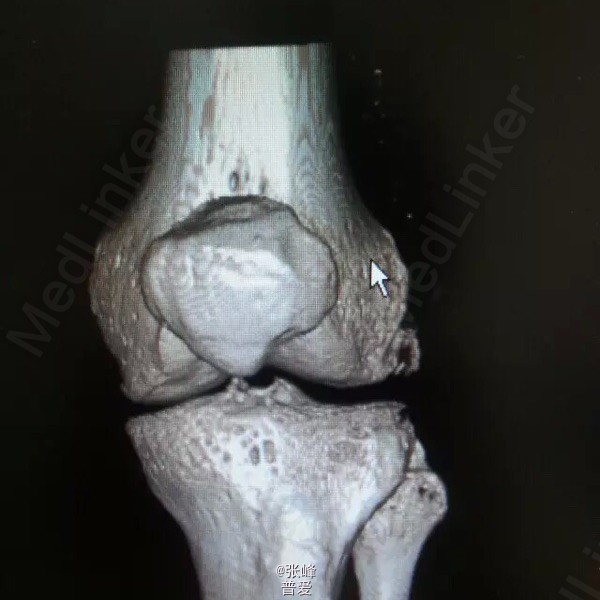

患者刘曙平,男,57岁。 左膝部肿痛、活动受限1天。 患者于昨天无明显诱因出现左膝肿胀,疼痛,伴活动受限。自行服药及局部外敷药治疗(具体不详),效果不明显,疼痛渐加重。为求进一步诊治,就诊我院,门诊了解病史、查体后以“左膝滑膜炎”收入院。 起病以来,精神一般,未进饮食,二便未解,体力尚好。 既往史:发现“高血压”4年,规律服用“倍他乐克”“波依定”,血压控制可;发现“痛风”20余年,目前症状控制一般。否认糖尿病、肝炎、结核等病史,否认药敏史。

诊断:左膝滑膜炎 诊疗计划:1.完善相关检查,如血尿常规分析、肝肾功能等。 2.对症治疗,观察左膝情况。 3.请示上级医师指导治疗。 者诉左膝部疼痛不适,无诉其他特殊不适,大小便正常。赵晶晶主治医师查房:患者根据既往病史、查体检查,目前考虑诊断左膝关节痛风性关节炎可能性大,暂以抗尿酸、对症支持及局部理疗,

患者诉左膝部疼痛较前明显好转,无诉其他特殊不适,大小便正常。谢主任示:患者经抗尿酸、局部理疗及对症支持等治疗,疼痛较前明显好转。拟行局部富血小板血浆注射,患者拒绝。拟明日办理出院,嘱院外继续治疗。严格低嘌呤饮食,禁烟禁酒,加强抗尿酸治疗。定期复查,建议每周我院门诊复诊。